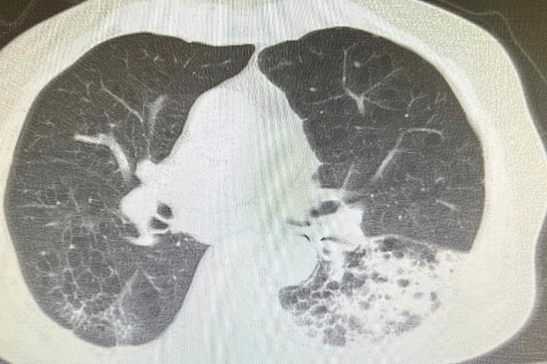

老人應該預防跌倒與嗆到才能延長壽命。 年紀大吞嚥困難常嗆到而不敢吃,產生營養不良。老是嗆入而產生吸入性肺炎而老是要住院治療,以前為了延長壽命減少嗆而接受插鼻胃管進食。但是現在為人性尊嚴與享受美食反對插鼻胃管,所以吸入性肺炎或意外嗆到而死案例增加。年紀大吃東西要小心 常常噎到甚至嗆進呼吸道。因為喉部肌肉萎縮與神經反射遲緩,食道蠕動較差所以導致吞嚥困難且易嗆進呼吸道(大的異物如假牙、骨頭等)而嚴重卡在在大氣管導致猝死。若中小異物卡在支氣管會產生塌陷與阻塞性肺炎,若睡覺口水嗆到至肺泡產生局部發炎,若是多次嗆至肺泡多次發炎產生肺纖維化。 吃東西假牙掉入左下肺支氣管產生阻塞性肺炎案例分享;九十五歲男性有抽煙史產生慢性阻塞性肺病病史且有攝護腺癌病史。最近因吃東西嗆到產生劇烈咳嗽與呼吸困難,且發現假牙不見了來院求診:胸部低劑量電腦斷層顧示右下肺有異物與阻塞牲肺炎(見圖)。緊急支氣管鏡檢並移出此異物。